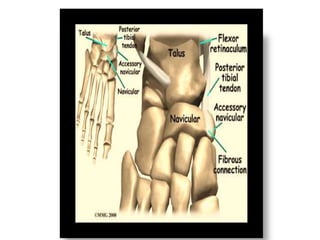

The accessory navicular sits posteromedial to the navicular , and it

ossifies between 9 and 11years of age.

It is seen radiographically with much variation, small to large, round to

triangular.

Its connection to the navicular may be fibrous, cartilaginous, or bony.